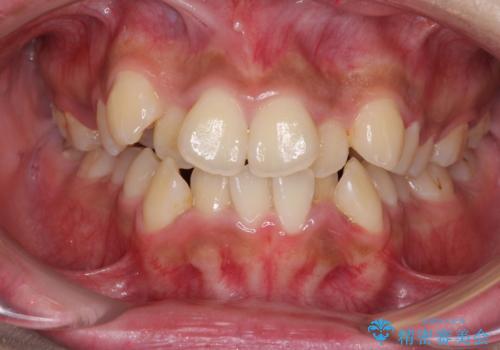

- 八重歯と上下前歯のでこぼこを気にして来院された患者様です。

上下前歯部叢生のスペース獲得のため、上下顎左右小臼歯各1歯(計4本)と全ての親知らずを抜歯して、矯正治療を行うこととしました。